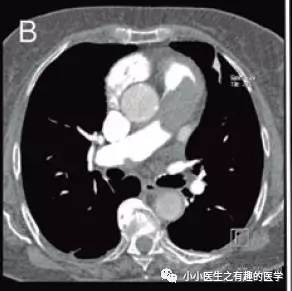

35岁女性,呼吸困难,咯血,胸痛。哈哈,哈哈,哈哈,典型的肺栓塞。

绝对的肺栓塞。

诊断慢性肺栓塞,治疗6月。

复查

星星,还是那颗星;月亮,还是那个月……

血栓,还是那么大滴哟,一个—–血—-栓。

最终诊断:肺动脉肉瘤。